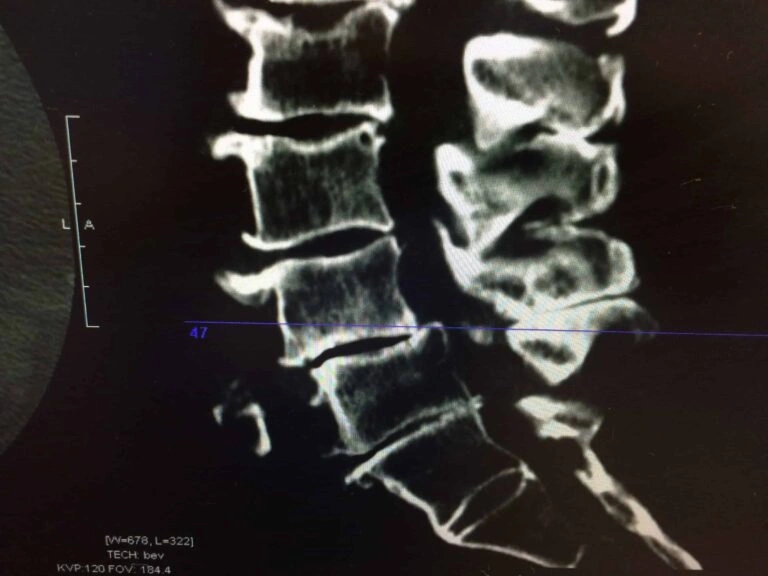

Spondylolisthesis happens when one vertebra slips out over the one below it. When this does cause symptoms, they are usually back and leg pain. Some severe cases can cause other,…